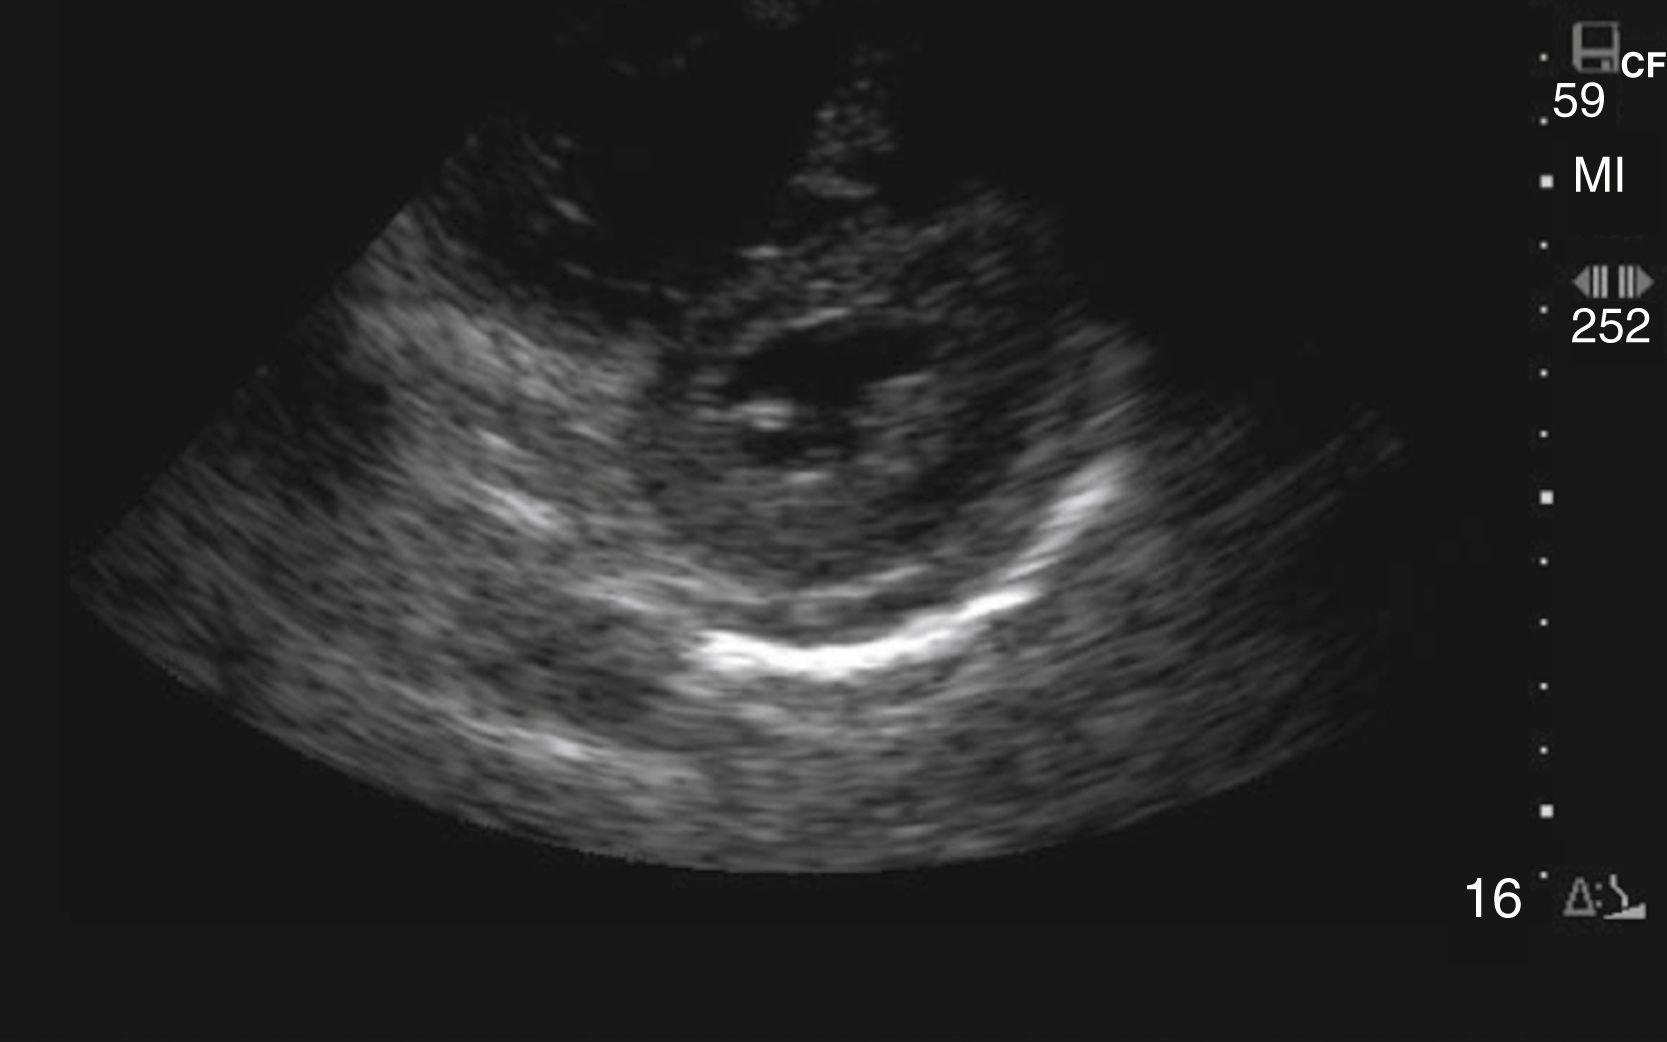

Assessment for global LV systolic function can be performed with visual estimation ( Video e3.10 ) and/or assessment of E-point septal separation (EPSS). EPSS is the distance between the anterior mitral valve leaflet and the ventricular septum measured using M-mode. A distance greater than 7 mm is abnormal, with larger measurements correlating to worsening systolic function. Emergency clinicians should recognize that accurate visual estimation of global LV systolic function requires experience and may prefer to categorize systolic function dichotomously as depressed or normal.

RV assessment is another useful tool for the emergency clinician when pulmonary embolism (PE) is high on the differential. With increasing right heart pressure, the RV dilates, squeezes poorly, and ultimately develops flattening of the interventricular septum, creating the “D” sign ( Figs. e3.12, e3.13 , and Video e3.11 ). The sparing of the RV apex is called the McConnell sign and is highly suggestive of PE. ,

Fig. e3.13

Parasternal short axis view with “D” sign signifying increased RV pressure.